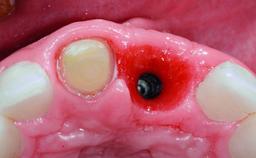

A 32-year-old female Caucasian patient with a compromised maxillary right central incisor was referred to us by a general dentist. Her chief complaints were discomfort and mobility of tooth 11 with unsatisfactory esthetics due to discoloration. The patient reported a previous trauma, some years earlier, as the origin of pathology on the afflicted tooth. Anamnesis was negative for any other dental or periodontal pathology in the remaining dentition. The patient did not take any medication and reported to be a light smoker (5–10 cigs/day). She had high esthetic expectations of her treatment. The extraoral examination revealed a high smile line with full exposure of her maxillary teeth and surrounding soft tissue in the area between the second premolars.

Bone Augmentation Horizontal|Simultaneous|Staged

Augmentation Materials Autogenous chips|Xenogenous|Membrane

Soft Tissue Grafting Staged

Bone Volume Deficient horizontally, requiring prior grafting